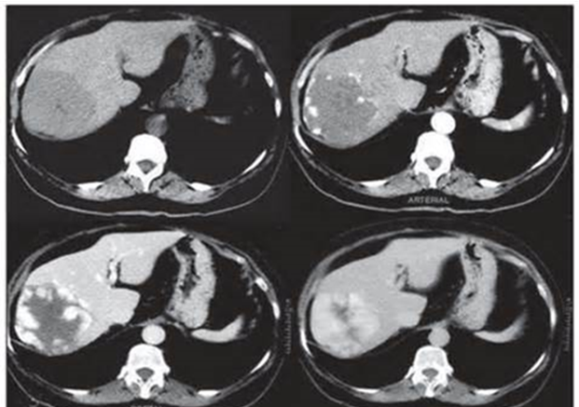

• Dəqiqləşdirmək üçün klinik əlamətlərlə yanaşı endokrin müayinə, tomoqrafiya və ssintoqrafiya aparılır.

• NET-in qaraciyər metastazlarının xarakterik xüsusiyyəti hipervaskulyar olmasıdır ki, bu da Doppler müayinəsində intensiv axın şəklində, kontrastlı müayinələrdə isə arterial fazada kontrastlaşma və venoz fazada yuyulma əlaməti ilə təyin edilir.

• Hormonal aktiv şişlərdə endokrin əlamətlərlə yanaşı qanda hormonların səviyyəsi artır.

• Funksional karsinoidlərdə sidikdə 5-hidroxiindol turşusunun təyini, adacıq şişlərində isə hormonların təyini diaqnozda faydalıdır.

• Adacıq şişlərinin yayılmasını və diaqnozunu dəqiqləşdirmək üçün PET-KT və somatostatins sintoqrafiyası faydalıdır.

• Histokimyəvi müayinədə xromoqrafin A və neyron – spesifik enolazanın tapılması diaqnozu dəqiqləşdirir.